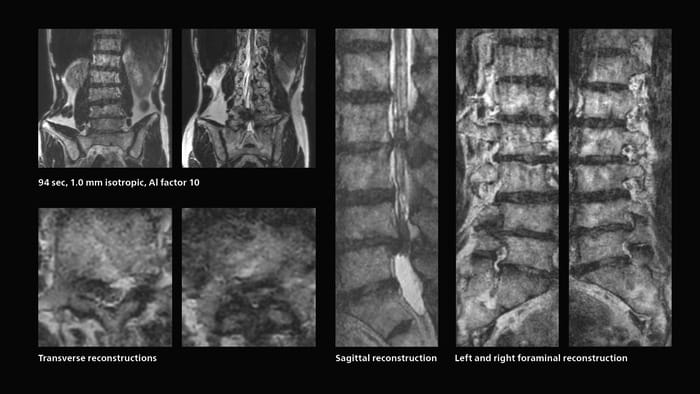

Faster lumbar spine exams are beneficial for patients with pain

Many patients who must undergo a lumbar spine examination suffer from back pain. For these patients it is difficult to maintain the imaging position long enough to successfully complete the examination. “In such cases, using SmartSpeed allows us to perform volume imaging, so that we acquire only one high resolution 3D sequence in a short time and then reconstruct the other orientations from that,” Dr. Katahira says.

“This is highly advantageous because the patient needs only endure a short exam time, whereas before it was necessary to acquire a larger number of sequences in total. We have seen that the shorter time has allowed us to scan patients who previously could not finish the exam. This is a great advantage.”

Fast lumbar spine imaging for successful exam of patient in pain

A patient arrived saying that undergoing MRI was not possible because of severe back pain and leg pain, was imaged with SmartSpeed in only 94 seconds. The scan was diagnostic and afterwards the patient confirmed that it only took a little while. Performed on Elition X.

Fast lumbar spine MRI with SmartSpeed of a patient in pain produced a successful isotropic diagnostic scan in only 94 minutes.

The hospital’s fast lumbar spine ExamCard includes T2W SpineVIEW, 1:40 min, 1.0 mm isotropic, acceleration factor 12.